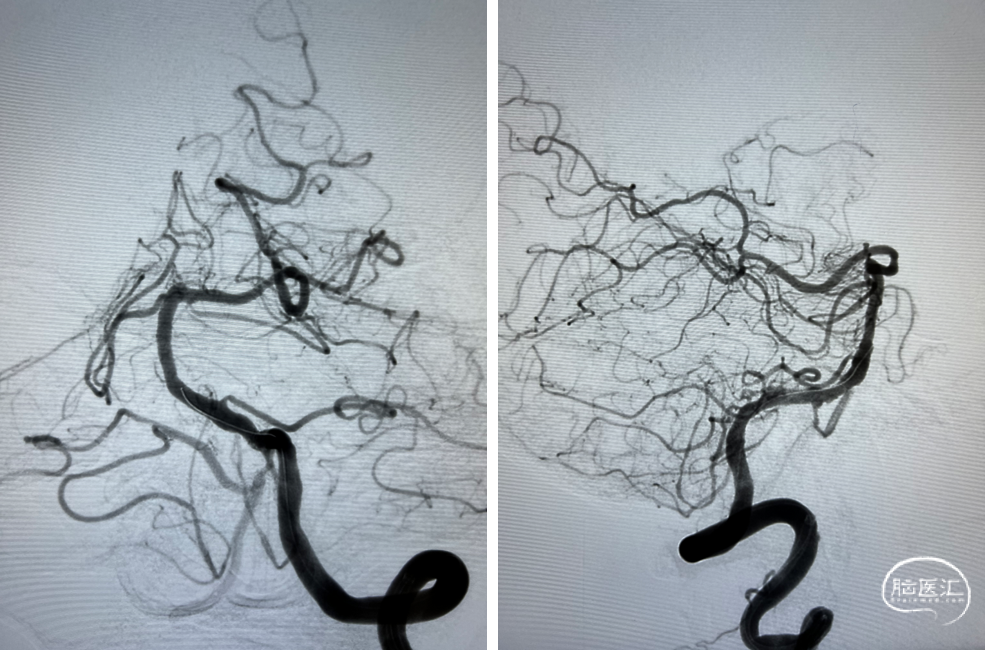

支架顺利到达病变位置到位。

充盈球囊,释放支架。

支架释放后。

术后影像及检查

赛诺神畅 NOVA颅内药物球扩支架是全球首款雷帕霉素颅内药物支架,含有药物涂层支架及快速交换球囊输送系统,术中通过性好,输送佳,可降低支架内再狭窄率,减少远期再发卒中风险。

1. 对于迂曲的后循环颅内病变,往往需要长鞘和中间导管支撑,维持通路的稳定,有助于球囊和支架的顺利到位;